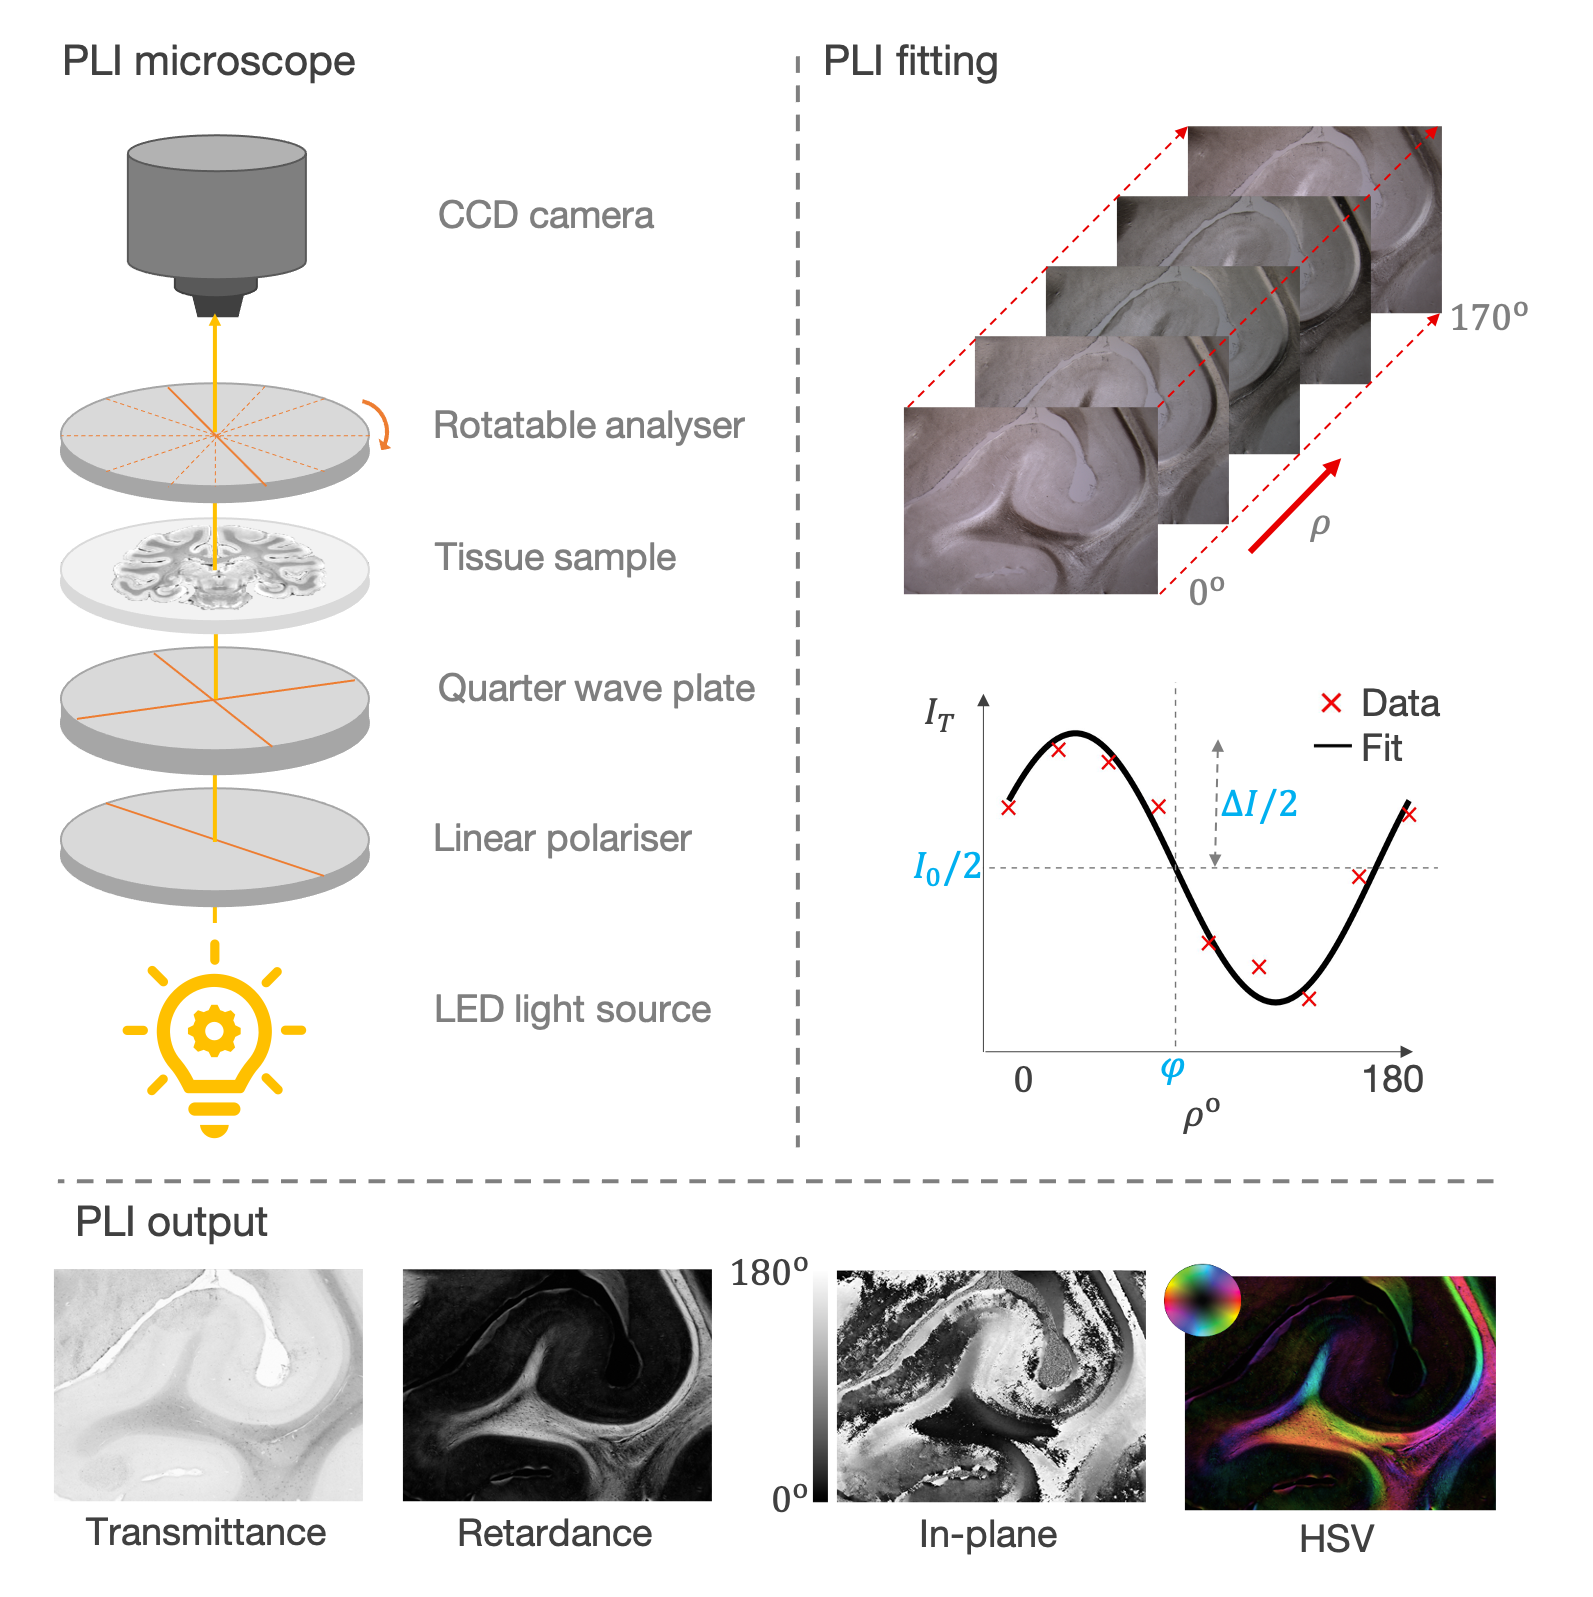

The PLI setup

In its most basic for, the PLI microscope is made of three components:

Optics to prepare the polarisation

The thin tissue sample (~50-100 μm thick)

The rotatable analyser and camera

Light from an LED polariser is first shone through a linear polariser and a crossed quarter wave-plate to generate circularly polarised light. The circularly polarised light is then transmitted through the tissue sample where birefringent material results in circular -> elliptical polarisation. Images are then acquired as the analyser (a second linear polariser) is rotated in discrete steps from ρ = 0-180o.

PLI outputs

A sinusoid is fitted to the measured intensity at each pixel (I) as a function of analyser rotation ρ

I = I0 / 2 (1 + sin(2ρ − 2φ) sin δ)

Maps of transmittance, retardance, and in-plane angle were derived from the sinusoid phase and amplitude.

The transmittance, I0, is twice the average intensity of light at the detector and is related to the amount of light extinguished by the sample.

The retardance, ΔI = |sin δ|, describes the ellipticity of the polarisation and is determined by both the quantity and birefringence of myelin, as well as its orientation (inclination) with respect to the imaging plane.

The in-plane angle, φ, describes optic axis which is assumed to align with the azimuth or in-plane angle of the fibre.

To aid interpretation, a composite hue-saturation-value (HSV) image is generated where the hue is defined by the in-plane angle and the value given by the retardance.